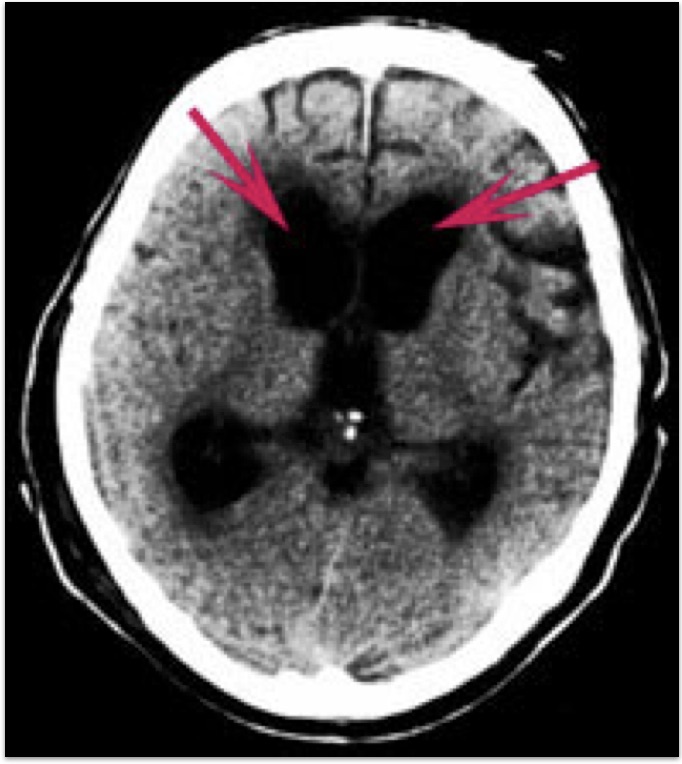

<くも膜下出血がわかりにくいCT画像>

くも膜下出血の診断にはCTによるクモ膜下腔の高吸収の検出が適しており、発症24時間以内の診断率は92%で、以降時間の経過とともに低下します。すなわち、発症して救急車ですぐに病院に来られた場合には、診断率がよいということになりますが、2−3日経ってから(幸い再破裂などなく)、来院された場合には診断率が低下いたしますので、場合によってはCTのみでは診断ができない、誤診するということもありえるのです。

<治療前:脳室拡大>

矢印は拡大した脳室